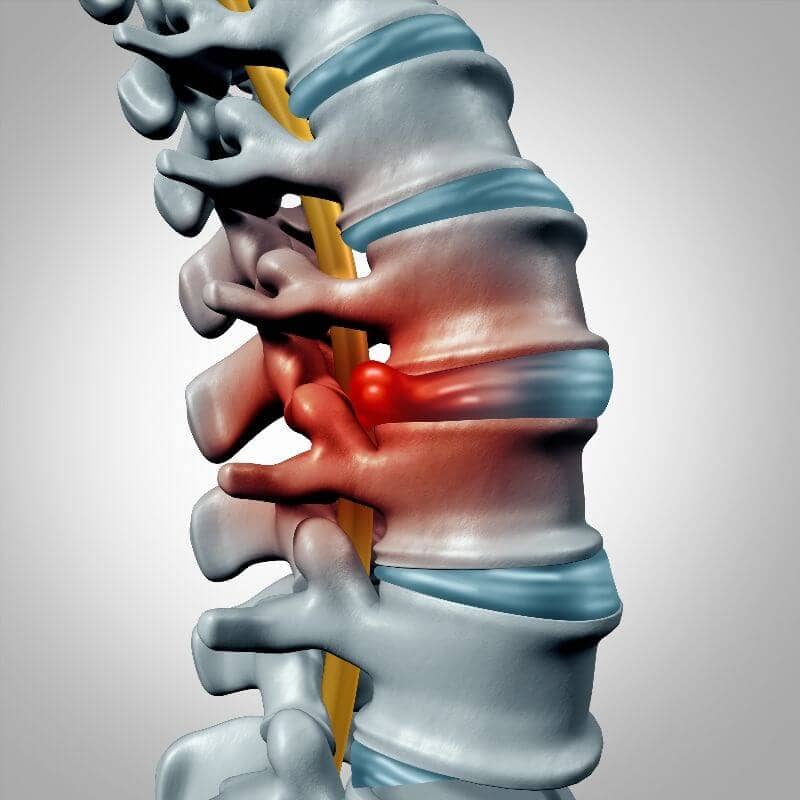

Soy médico especialista en cirugía neurológica y columna vertebral, con la experiencia profesional en el uso de la tecnología más innovadora a nivel mundial, para lograr los mejores resultados en las enfermedades del cerebro y la columna vertebral.

Soy médico especialista en cirugía neurológica y columna vertebral, con la experiencia profesional en el uso de la tecnología más innovadora a nivel mundial.